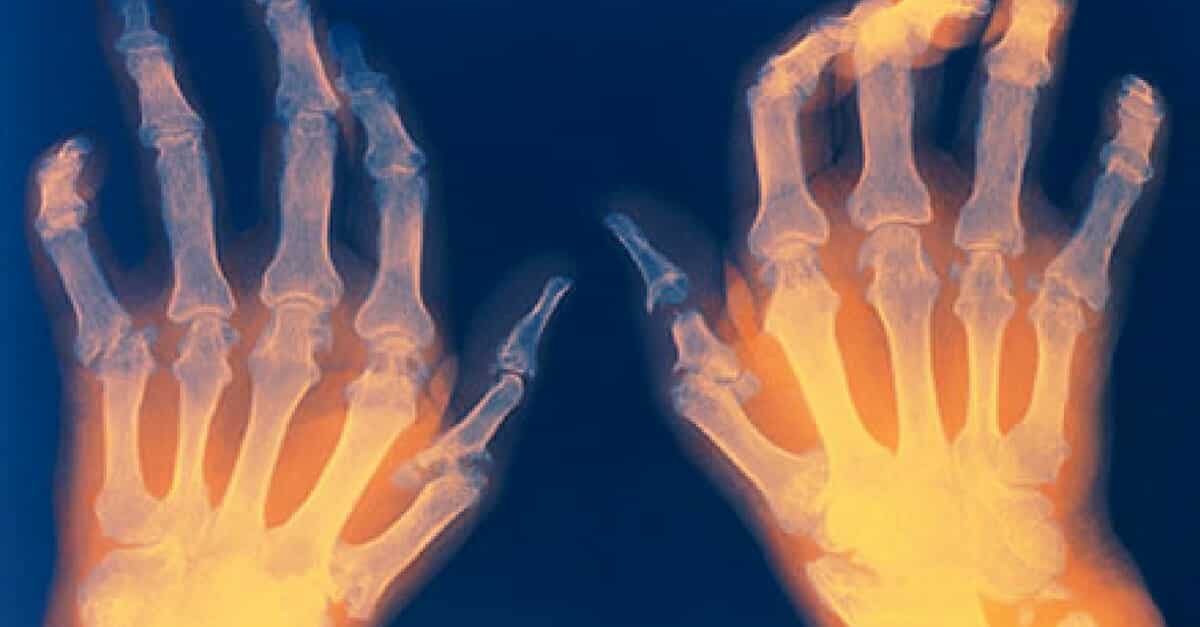

8. Artrite Reumatoide

Por fim, este tipo de artrite é o mais comum e acontece por problema no sistema imunológico, atacando não só a cartilagem, mas os tecidos e revestimento da articulação. Causa dor, inchaço, vermelhidão, rigidez e perda das funções articulares no local afetado.